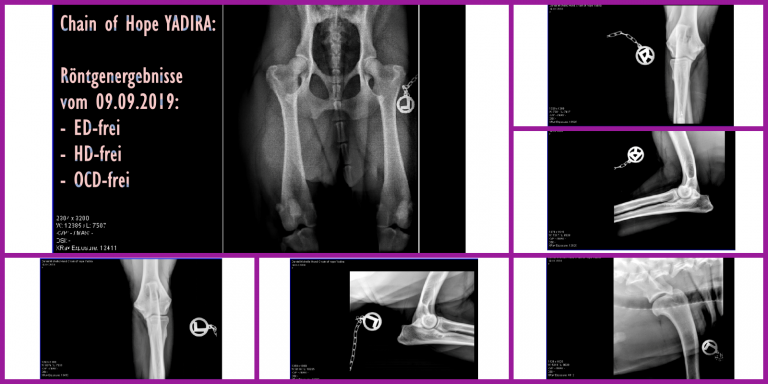

Health:

- HD-free

- ED-free

- OCD-free